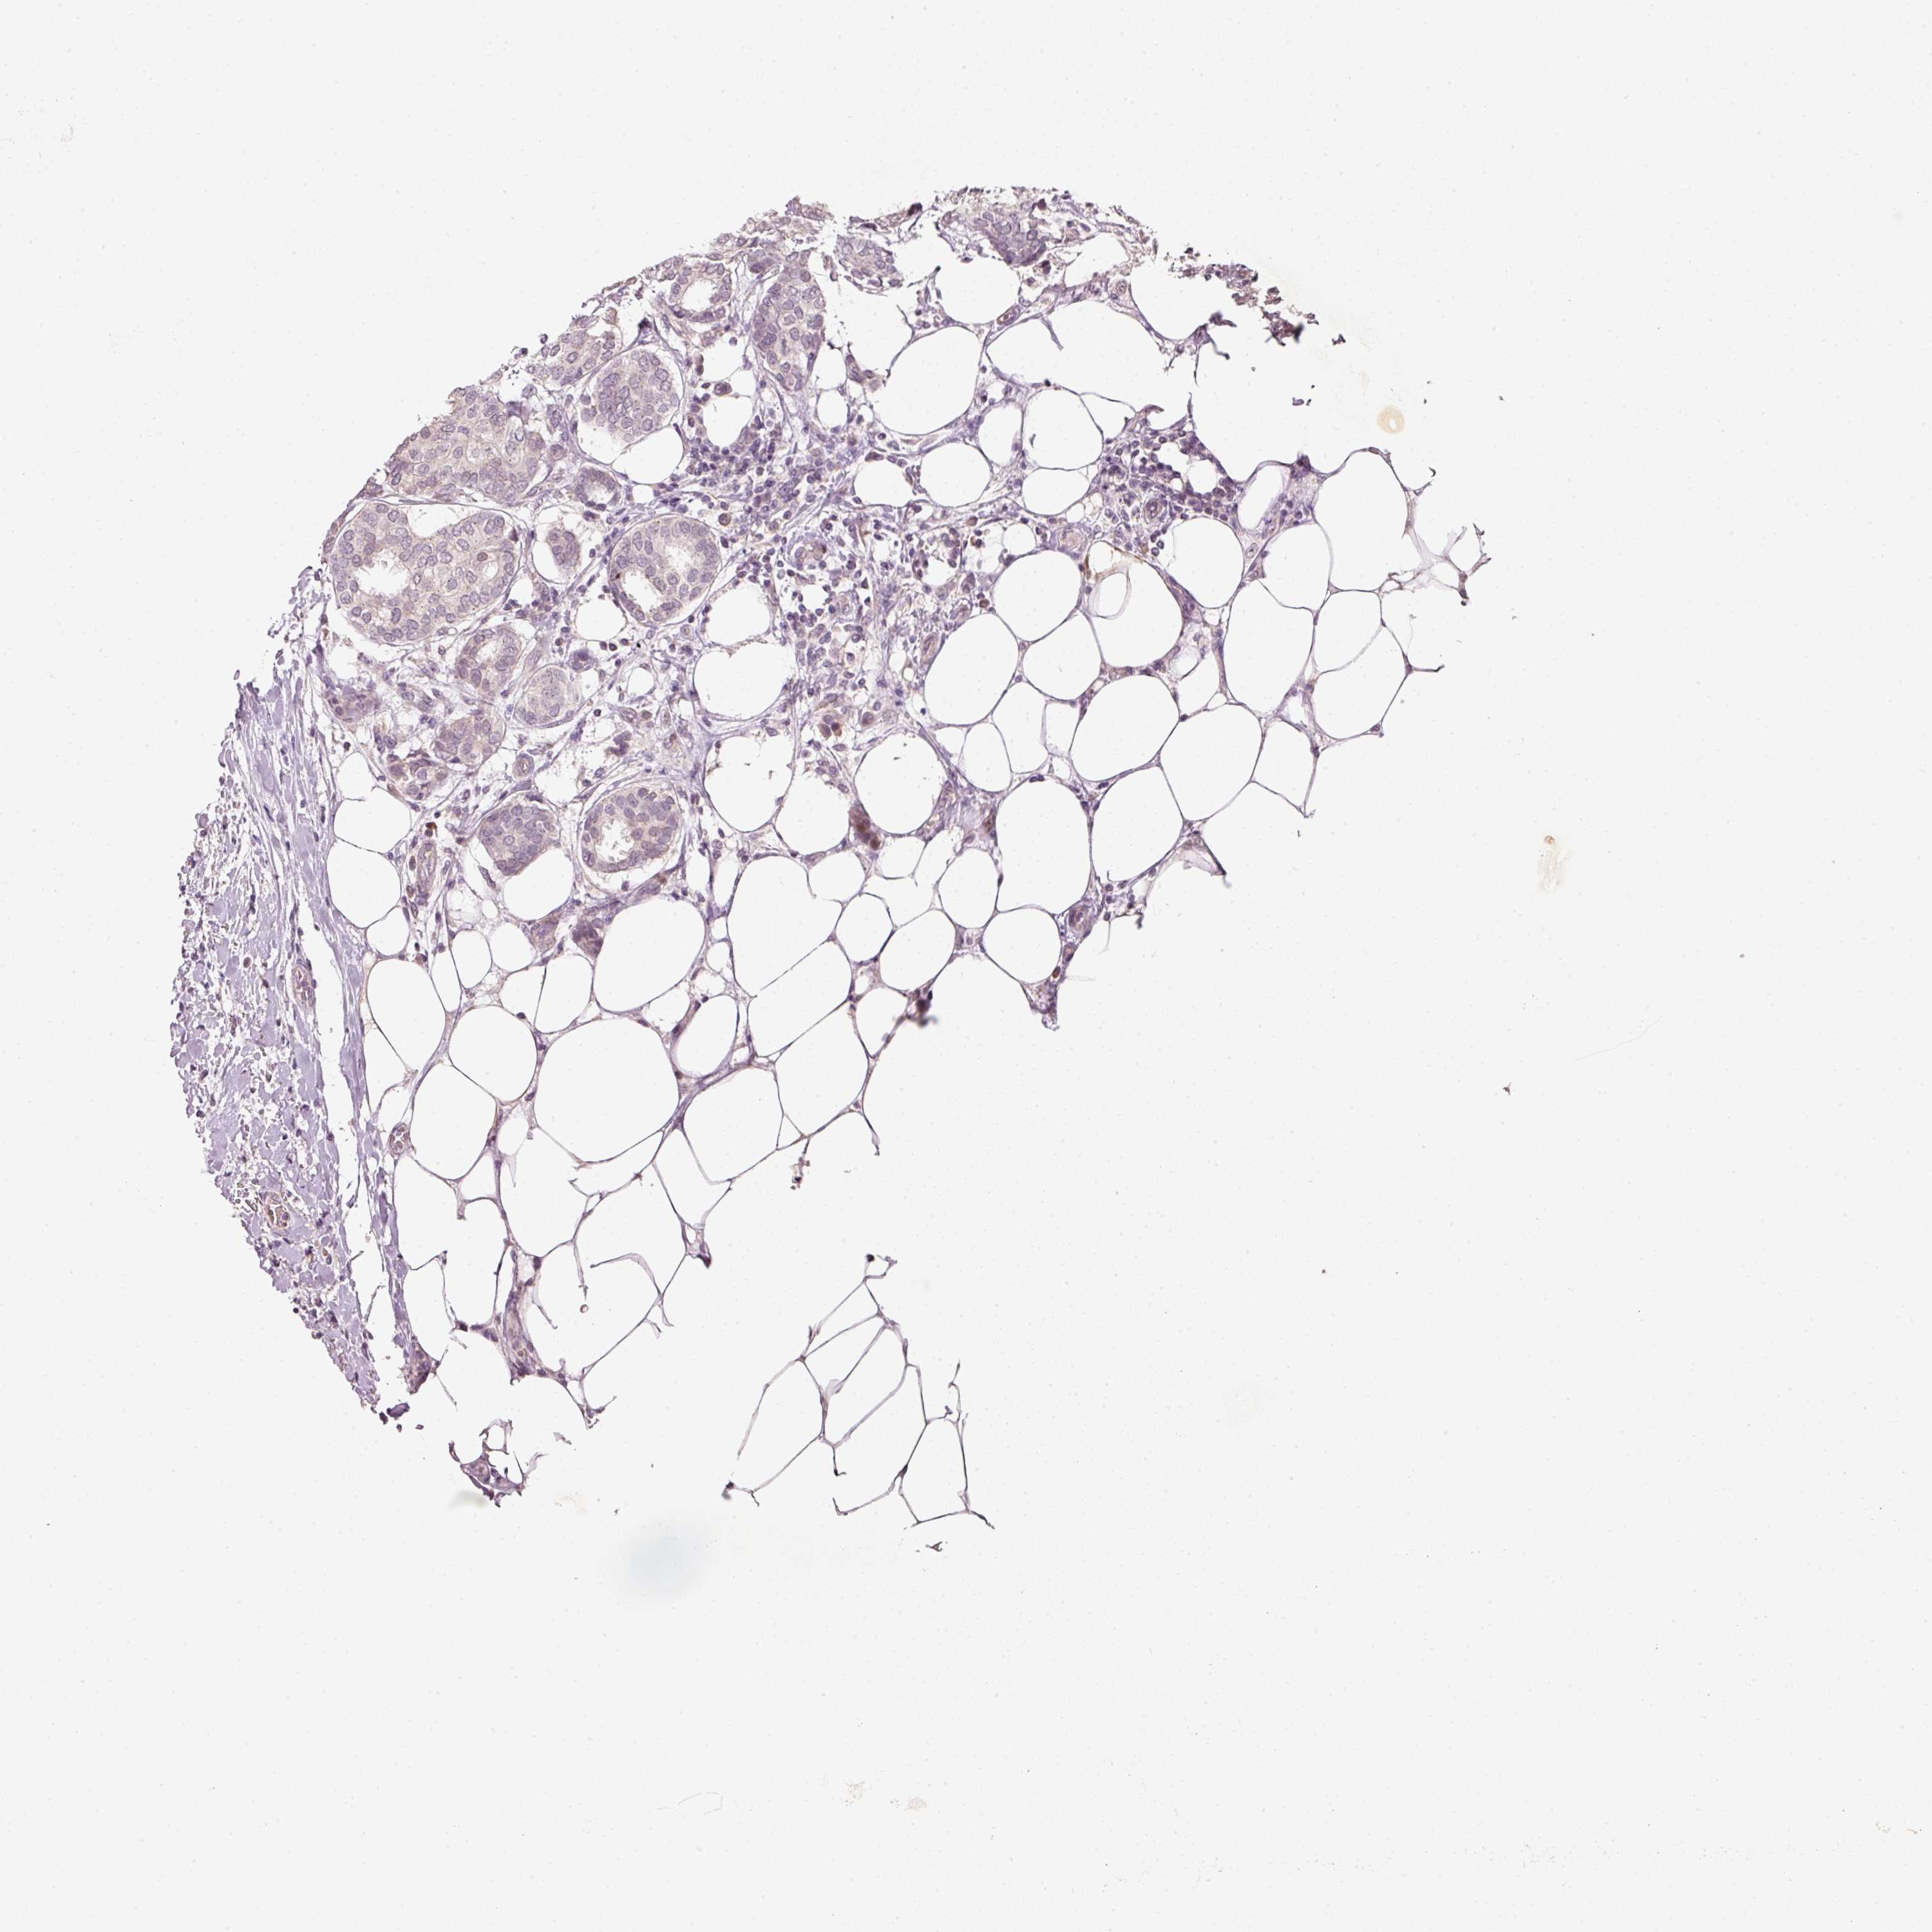

CANCER BREAST CANCER Show tissue menu

BRCA TCGA BRCA VALIDATION PROTEIN EXPRESSION